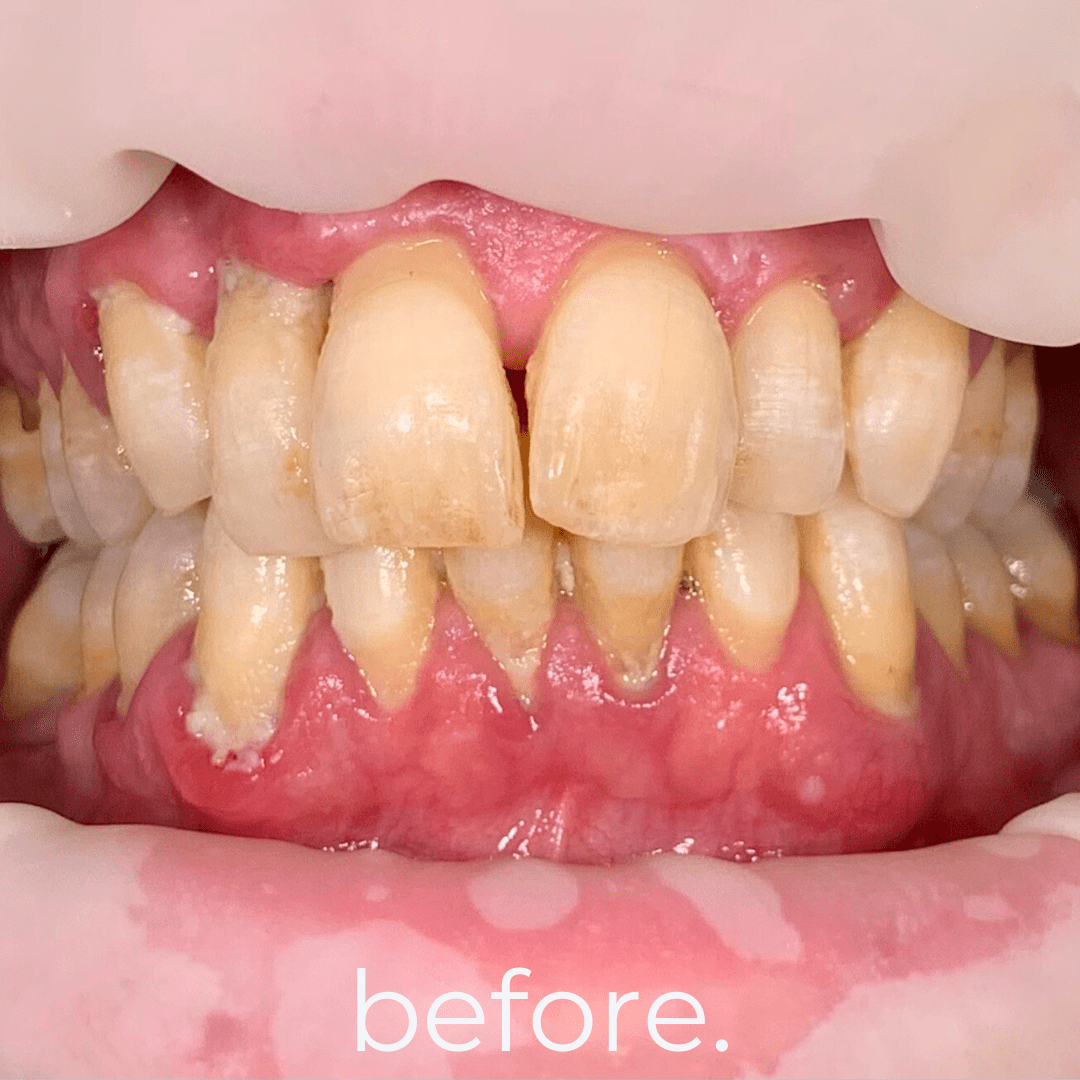

Full mouth rehabilitation is a comprehensive dental treatment designed to restore both function and aesthetics for patients with severely worn, damaged, missing, or failing teeth.

Treatment may include a combination of:

* crowns

* veneers

* dental implants

* bridges

* gum treatment

* bite rehabilitation

Each treatment plan is customized based on the patient’s oral condition and long-term goals.